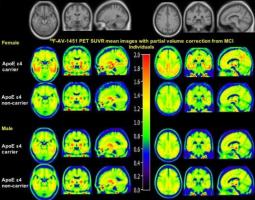

Actualité publiée il y a 5 années 1 semaineALZHEIMER : Le sexe affecte tau dans le cerveau